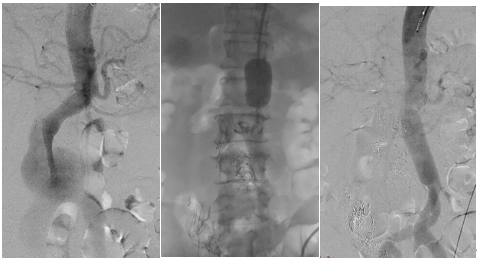

患者术前造影,动脉瘤最大直径达6.9厘米(左);术者用主动脉大球囊阻断腹主动脉(中);血管置换术后造影,血流恢复正常(右)